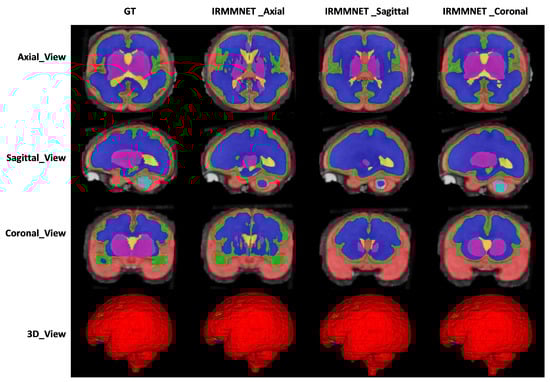

Table 1 tabulates the DSC, HD95, sensitivity, and specificity values of the proposed segmentation model, IRMMNET, with the axial, sagittal, and coronal views (IRMMNET-Axial, IRMMNET-Sagittal, and IRMMNET-Coronal). IRMMNET-Coronal obtained better performance for all classes than IRMMNET with the axial and sagittal planes. It achieved DSC, HD95, sensitivity, and specificity scores of 0.789, 21.56, 0.818, and 0.976, respectively.

Figure 9 shows the proposed IRMMNET model’s segmentation maps for the axial, sagittal, and coronal planes. In addition, 2D and 3D volumetric views of the segmentation images are shown in Figure 9 for the axial, sagittal, and coronal planes. It can be visibly noticed that the coronal-view model generated accurate segmentation masks, in which the predictions for the deeper and smaller classes were close to the GT. It should be noted that the proposed model was initially tried on the 2D axial slices, but the predicted segmented images yielded a bad prediction for the deep classes. Therefore, the proposed segmentation model was applied to the three views’ 2D slices (axial, sagittal, and coronal) for fetal brain segmentation. Among the predicted segmentation results for the fetal brain, the 2D coronal view produced the best results.

Figure 9. The segmentation maps of the proposed model with different views.

Entropy 24 01708 g009